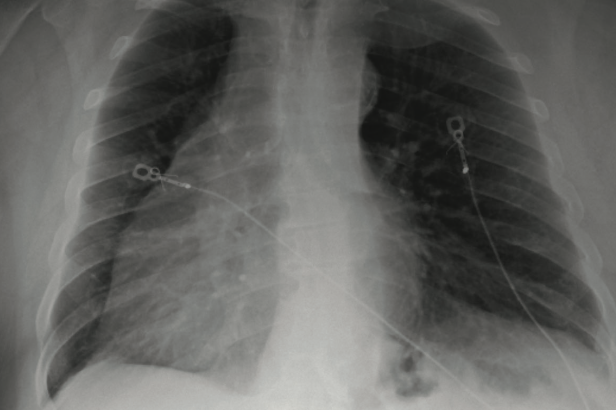

This article collects 3 photo-based case reports about conditions affecting the lungs, including large pulmonary embolus with unilateral hyperlucent lung, atelectasis, and Streptococcus pneumoniae...